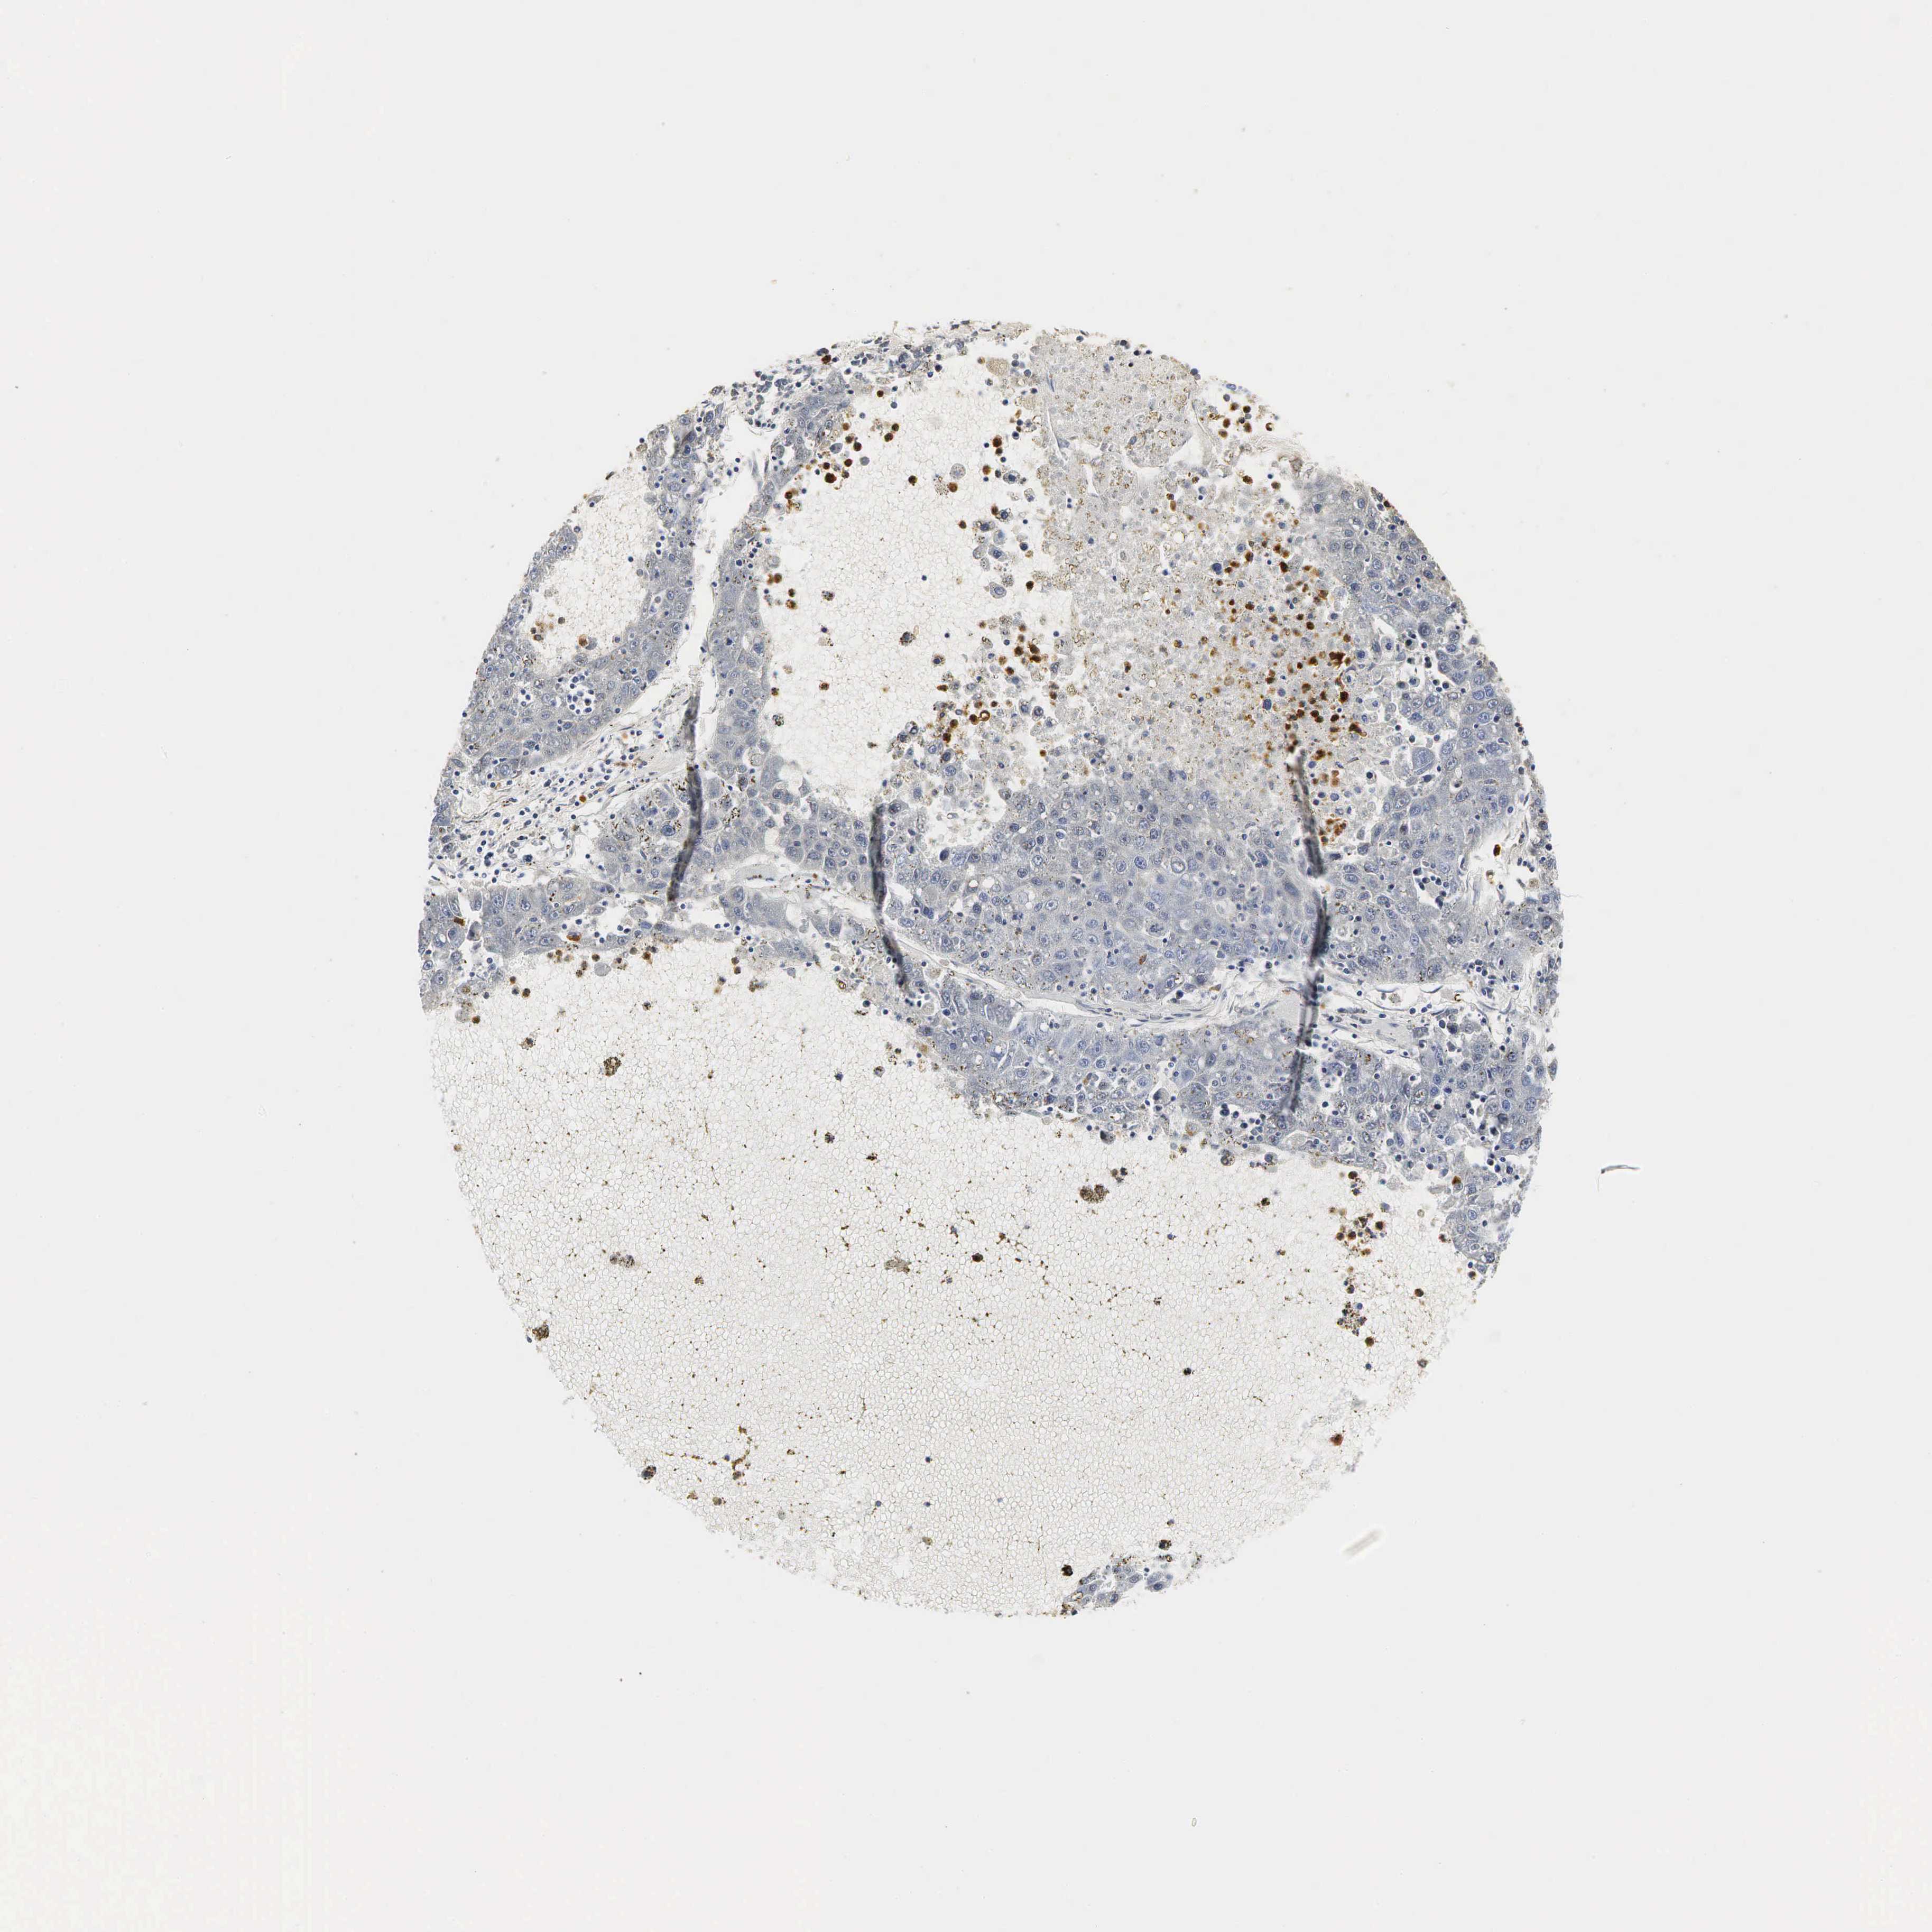

LIVER CANCER - Protein expressioni

A mouse-over function shows sample information and annotation data. Click on an image to view it in a full screen mode. Samples can be filtered based on level of antibody staining by selecting one or several of the following categories: high, medium, low and not detected. The assay and annotation is described here.

Note that samples used for immunohistochemistry by the Human Protein Atlas do not correspond to samples in the TCGA dataset.

Antibody stainingi

Antibody staining in the annotated cell types in the current human tissue is reported as not detected, low, medium, or high, based on conventional immunohistochemistry profiling in selected tissues. This score is based on the combination of the staining intensity and fraction of stained cells.

Each image is clickable and will lead to virtual microscopy that enables deeper exploration of all samples and also displays staining intensity scores, fraction scores and subcellular localization as well as patient and tissue information for each sample.

Cholangiocarcinoma

Carcinoma, Hepatocellular, NOS

Carcinoma, metastatic, NOS